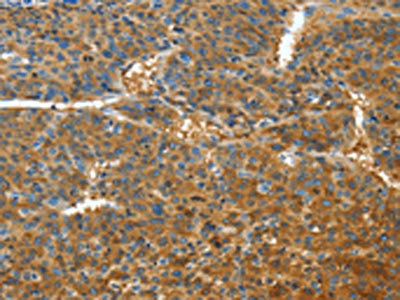

The image on the left is immunohistochemistry of paraffin-embedded Human liver cancer tissue using CSB-PA108957(TNFSF13B Antibody) at dilution 1/30, on the right is treated with fusion protein. (Original magnification: ×200)

The image on the left is immunohistochemistry of paraffin-embedded Human lymphoma tissue using CSB-PA108957(TNFSF13B Antibody) at dilution 1/30, on the right is treated with fusion protein. (Original magnification: ×200)